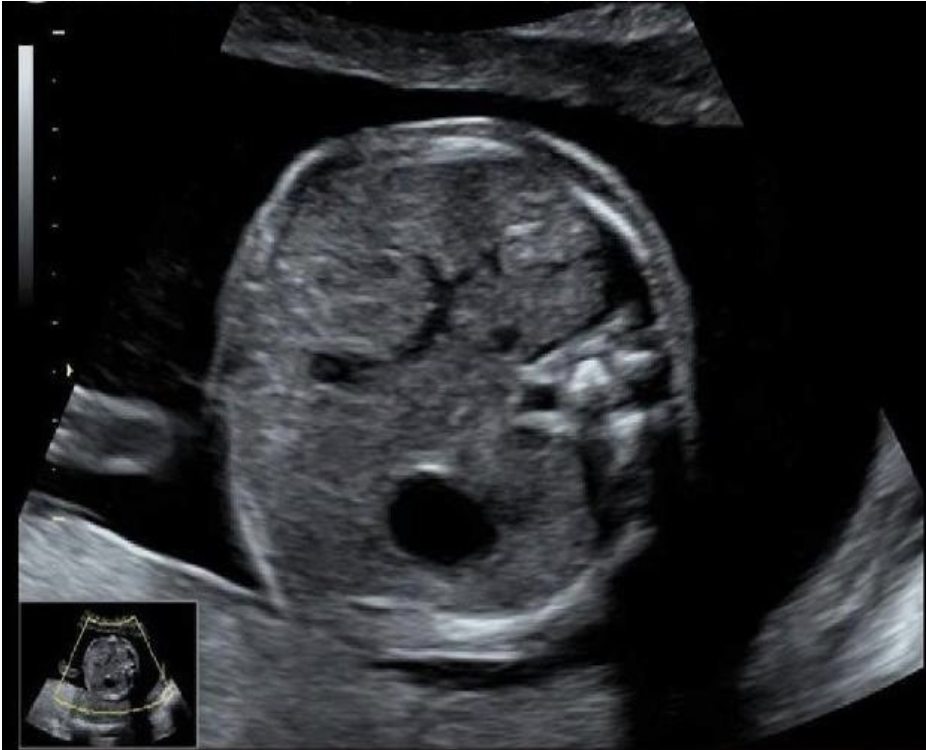

what maternal serum level will be increased

.

this is frog eyes aka anencephaly

a) inhibin A

b) estriol

c) delta OD450

d) AFP